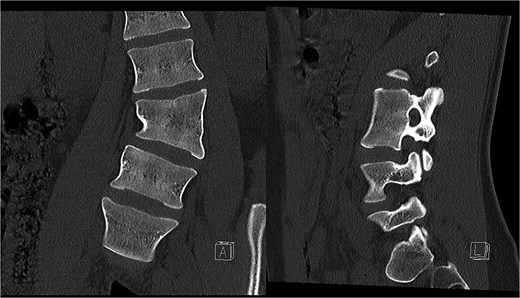

Preoperative CT demonstrating L3 hemivertebra; anteroposterior view (A) on the left side of the image, and lateral view (L) on the right side of the image.